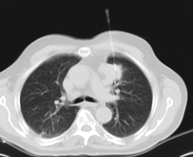

- TC Tórax

Prueba diagnóstica que consiste en obtener imágenes del tórax de alta definición anatómica (pulmones, corazón, mediastino, grandes vasos, caja torácica, etc.) mediante el empleo de un equipo de TC (Tomografía Computarizada). Dichas imágenes se estudian posteriormente en una estación de trabajo que permite reconstrucciones bidimendionales en diferentes planos del espacio y también reconstrucciones 3D (volumétricas). Algunos estudios requieren el empleo de contraste yodado para mejorar la definición de las imágenes.